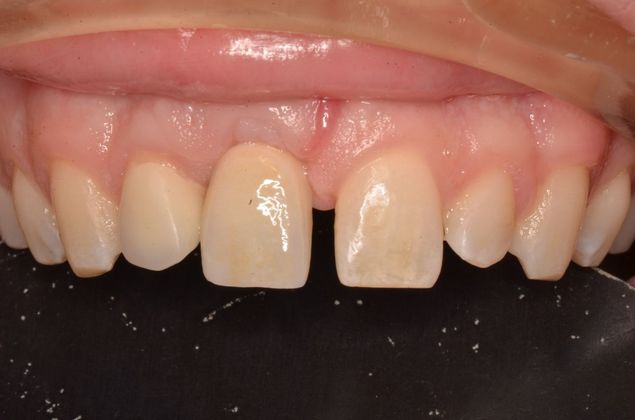

Replacing a missing upper central with an implant and a screw retained implant crown